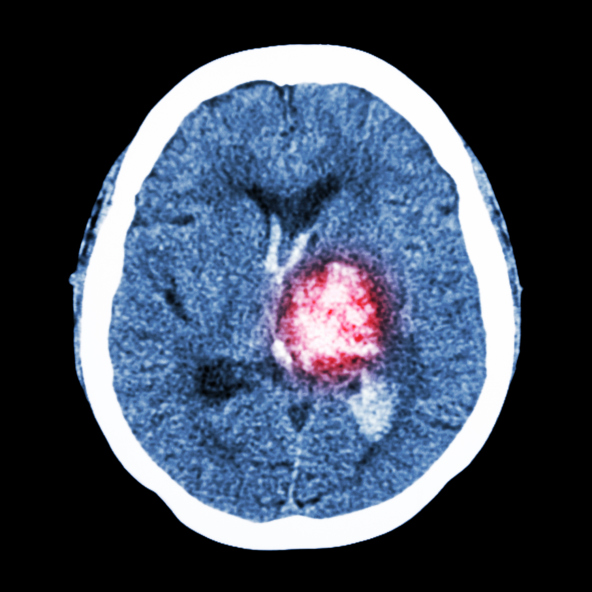

How to deal with memory loss after stroke

Our body functions mainly in part with our circulatory system. Every part of our body requires blood, which flows out from the heart and then back into the heart. When there is an interruption in blood flow, it can lead to some negative health consequences. One major organ to point out which requires much blood ...click here to read more